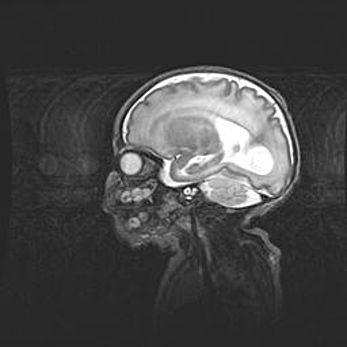

Лейкомаляция с кистозно-глиозной дегенерацией головного мозга.

Возраст: 2 месяца 25 дней

Вес: 6400 г

Окружность головы: 40 см

Срок гестации: 41 неделя

Лейкомаляцию относят к ишемически-гипоксическим повреждениям головного мозга, диагностируемым у новорожденных. При лейкомаляции в головном мозге обнаруживают очаги некроза, возникшие после тяжелой гипоксии и нарушения кровотока. В процессе морфогенеза очаги проходят три стадии: 1) развития некроза, 2) резорбции и 3) формирования глиозного рубца или кисты. Перивентрикулярная лейкомаляция (ПЛ) встречается примерно в 12% случаев среди новорожденных, обычно – у недоношенных детей, причем, частота ее зависит от массы, с которой младенец появился на свет. Наибольшее число малышей страдает лейкомаляцией, если масса при рождении 1500-2500 г.